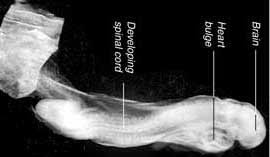

Ketiga ayat Al-Quran ini berbicara tentang tahapan-tahapan perkembangan embrio yang beragam secara sangat rinci. Pertama nutfah itu tersimpan didalam tempat yang kokoh (rahim). Kemudian dijadikan ‘alaqa’. Kata ‘alaqa’ ini mempunyai tiga buah makna:

Alaqa berarti ‘sesuatu yang menempel’ dan kita tahu bahwa pada tahap awalnya, embrio itu menempel pada dinding rahim dan terus menempel hingga lahir.

Alaqa berarti ‘sesuatu yang tampak seperti seekor lintah’ pada tahap-tahap awal, embrio itu tampak seperti seekor lintah. Selain memang ia tampak seperti seekor lintah, dia juga menerima pasokan (menghisap) darah dari sang ibu.

Alaqa berarti ‘segumpal darah’. Karena pada jaman sekarang ini, dengan adanya banyak pakar termasuk Prof. Keith Moore mengatakan, Bahwa pada tahap perkembangan sebuah embrio disamping tampak seperti seekor lintah, juga tampak seperti segumpal darah, karena pada tahap-tahap awal perkembangan ‘alaqa’ yakni pada masa tiga atau empat pekan, segumpal darah itu akan terbungkus dengan serat-serat pembuluh. Dan selama pekan ketiga dari perkembangan awal embrio tersebut, sirkulasi darah belum terjadi, itu baru terjadi pada tahap berikutnya. Oleh karena itu tampak seperti segumpal darah. Jika anda perhatikan ringkasannya, setelah dilakukan pengguguran kandungan, anda bisa saksikan bahwa ‘alaqa’ itu tampak seperti segumpal darah.

Tahapan-tahapan perkembangan embrio yang terdapat didalam Al-Qur’an hanyalah berdasarkan atas penampakkan (rupa) yang tampil ‘seperti seekor lintah’ atau ‘tampak seperti segumpal darah’. ‘Alaqa’ itu diciptakandari sesuatu yang tampak seperti ‘segumpal darah’ atau ‘seperti seekor lintah’ atau ‘sesuatu yang menempel’. Bahwa sebelum terbentuknya otot-otot dan tulang-tulang rawan, terbentuk dahulu tulang belulang. Tulang-belulang itu terbentuk bersamaan.

Pada saat ini, ilmu embriologi menjelaskan bahwa awalnya otot-otot dan tulang-tulang mereka terbentuk bersama-sama antara hari yang kedua puluh lima dan hari yang keempat puluh.

Setelah itu ia akan tampak memiliki kerangka. Bahkan pada tahapan ini, ketika tulang-tulang telah terbentuk, otot-otot belum terbentuk. Berikutnya setelah pekan ketujuh dan mulai masuk pekan kedelapan, otot itu mulai terbentuk.